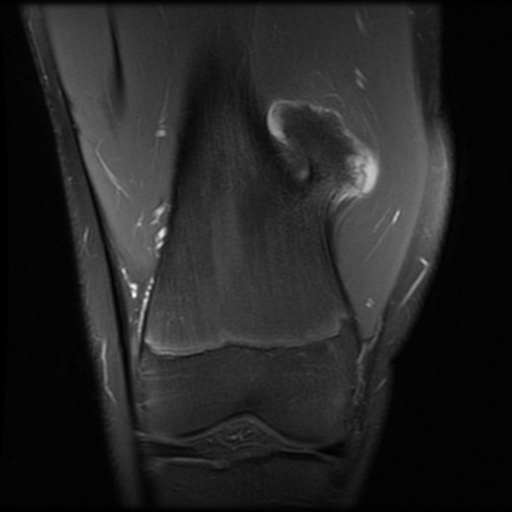

Um welchen Knochentumor handelt es sich auf dieser coronaren Schicht einer PD-fs MRT des distalen Femurs? Was würde auf eine maligne Transformation hinweisen?